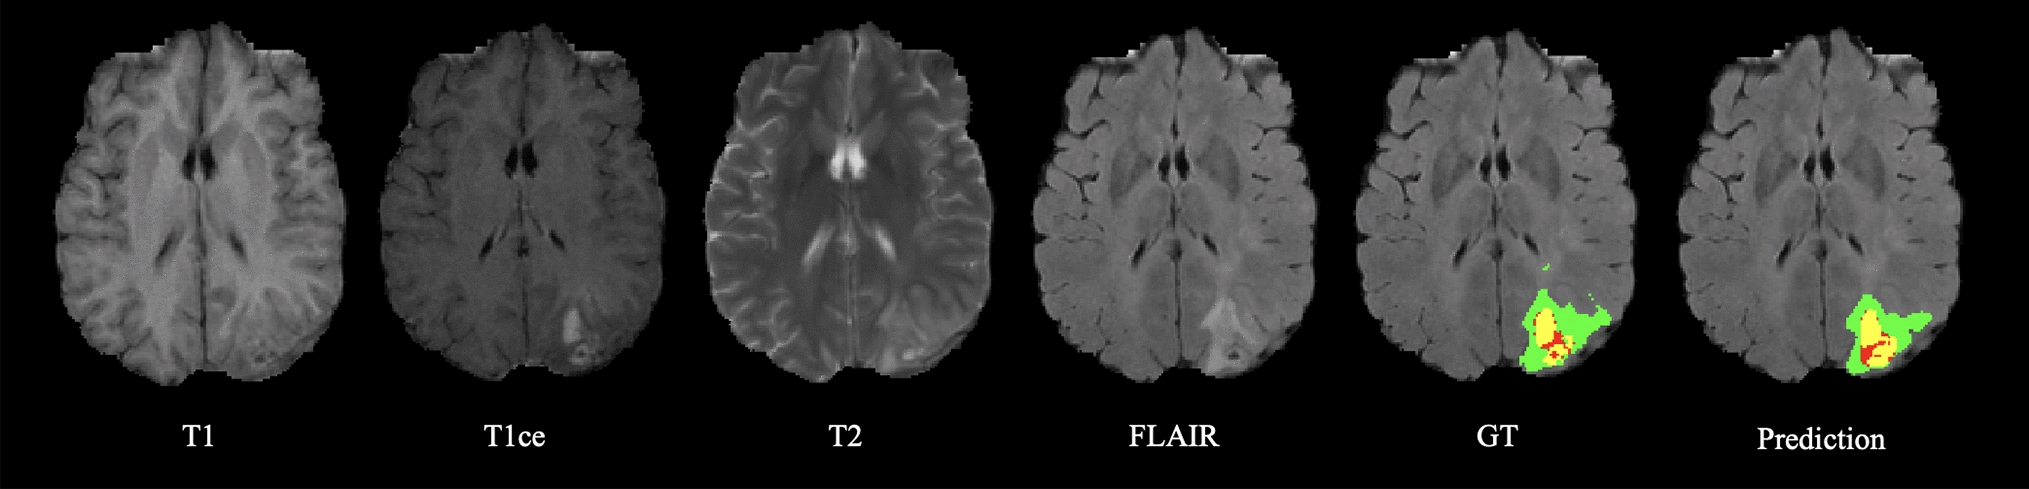

Fig. 1

Representative visual segmentation results of the proposed region-based EDL method on the BraTS 2020 test set. The labels are enhancing tumor (yellow), edema (green), and necrotic and non-enhancing tumor (red)

Our method generated comparable segmentation results with the GT labels, as visualized in Fig. 1. The quantitative results of our methods averaged over three tumor subregions are compared in Table 1. Although the proposed DICE and wDICE loss functions achieved the highest Dice scores (0.791 and 0.793) among all EDL-based methods, Ensemble and Dropout methods performed slightly more accurately in segmentation (0.807 and 0.804). The success of Ensemble and Dropout was attributed to the variance reduction by combining predictions prone to various errors. However, the dominance of the proposed region-based losses in all EDL frameworks still proved their effectiveness in improving EDL in segmentation performance. Compared to CE-based or MSE-based losses, the DICE-based losses significantlly improved the Dice score by 0.01.